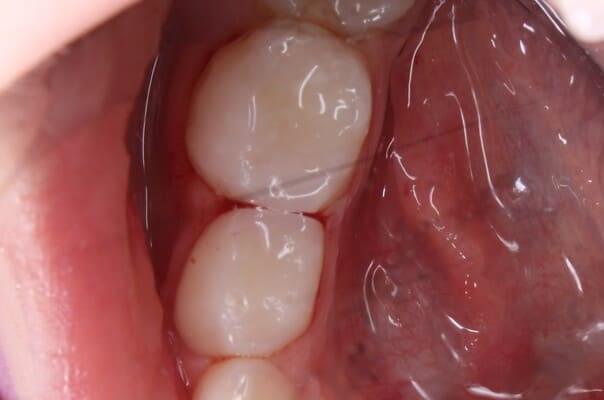

Поява перших постійних зубів, а це шості зуби, відбуваються, коли дитина ще не може, як слід провести їх гігієну та попіклуватись про їх здоров’я. Тому, на жаль вони і вражаються карієсом досить швидко. Пацієнт ще маленький – 6 років, а лікування потребує дорослого: зі знеболенням та ізоляцією. Саме таке і було проведене в даному випадку: зуб очищений від інфікованих тканин, відновлений фотополімерним матеріалом і готовий довго служити юному господарю.